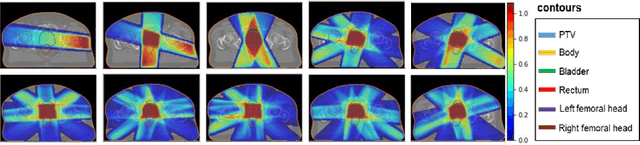

Abstract:We propose to develop deep learning models that can predict Pareto optimal dose distributions by using any given set of beam angles, along with patient anatomy, as input to train the deep neural networks. We implement and compare two deep learning networks that predict with two different beam configuration modalities. We generated Pareto optimal plans for 70 patients with prostate cancer. We used fluence map optimization to generate 500 IMRT plans that sampled the Pareto surface for each patient, for a total of 35,000 plans. We studied and compared two different models, Model I and Model II. Model I directly uses beam angles as a second input to the network as a binary vector. Model II converts the beam angles into beam doses that are conformal to the PTV. Our deep learning models predicted voxel-level dose distributions that precisely matched the ground truth dose distributions. Quantitatively, Model I prediction error of 0.043 (confirmation), 0.043 (homogeneity), 0.327 (R50), 2.80% (D95), 3.90% (D98), 0.6% (D50), 1.10% (D2) was lower than that of Model II, which obtained 0.076 (confirmation), 0.058 (homogeneity), 0.626 (R50), 7.10% (D95), 6.50% (D98), 8.40% (D50), 6.30% (D2). Treatment planners who use our models will be able to use deep learning to control the tradeoffs between the PTV and OAR weights, as well as the beam number and configurations in real time. Our dose prediction methods provide a stepping stone to building automatic IMRT treatment planning.